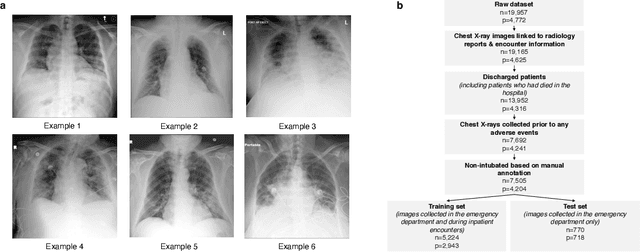

During the COVID-19 pandemic, rapid and accurate triage of patients at the emergency department is critical to inform decision-making. We propose a data-driven approach for automatic prediction of deterioration risk using a deep neural network that learns from chest X-ray images, and a gradient boosting model that learns from routine clinical variables. Our AI prognosis system, trained using data from 3,661 patients, achieves an AUC of 0.786 (95% CI: 0.742-0.827) when predicting deterioration within 96 hours. The deep neural network extracts informative areas of chest X-ray images to assist clinicians in interpreting the predictions, and performs comparably to two radiologists in a reader study. In order to verify performance in a real clinical setting, we silently deployed a preliminary version of the deep neural network at NYU Langone Health during the first wave of the pandemic, which produced accurate predictions in real-time. In summary, our findings demonstrate the potential of the proposed system for assisting front-line physicians in the triage of COVID-19 patients.